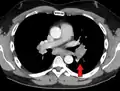

Hilar adenopathy especially on the person's left (AP CXR)

Hilar adenopathy especially on the person's left (lateral CXR)

Hilar adenopathy especially on the person's left (coronal CT)

Hilar adenopathy especially on the person's left (transverse CT)